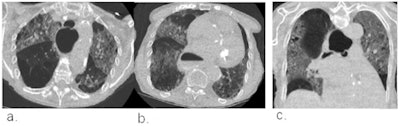

Example chest CT scans of a patient with a true-positive CO-RADS 4 score. (a,b) Two axial slices and (c) a coronal slice of a 79-year-old female with nine days of symptoms. CT shows diffuse ground-glass opacities close to visceral pleural surfaces but superimposed on emphysematous changes. Also note the widened esophagus. COVID-19 was RT-PCR confirmed. Images courtesy of the RSNA.

Example chest CT scans of a patient with a true-positive CO-RADS 4 score. (a,b) Two axial slices and (c) a coronal slice of a 79-year-old female with nine days of symptoms. CT shows diffuse ground-glass opacities close to visceral pleural surfaces but superimposed on emphysematous changes. Also note the widened esophagus. COVID-19 was RT-PCR confirmed. Images courtesy of the RSNA. Example chest CT scans of a patient with a false-positive CO-RADS 4 score. (d, e) Two axial slices and (f) a coronal slice of a 51-year-old female with two days of symptoms. CT shows bilateral multifocal areas of consolidation with halo and subtle areas of ground glass without contact to visceral pleural surfaces. RT-PCR for SARS-CoV2 was repeatedly negative and an alternative diagnosis was established with a blood culture-confirmed line sepsis. Images and caption courtesy of the RSNA.